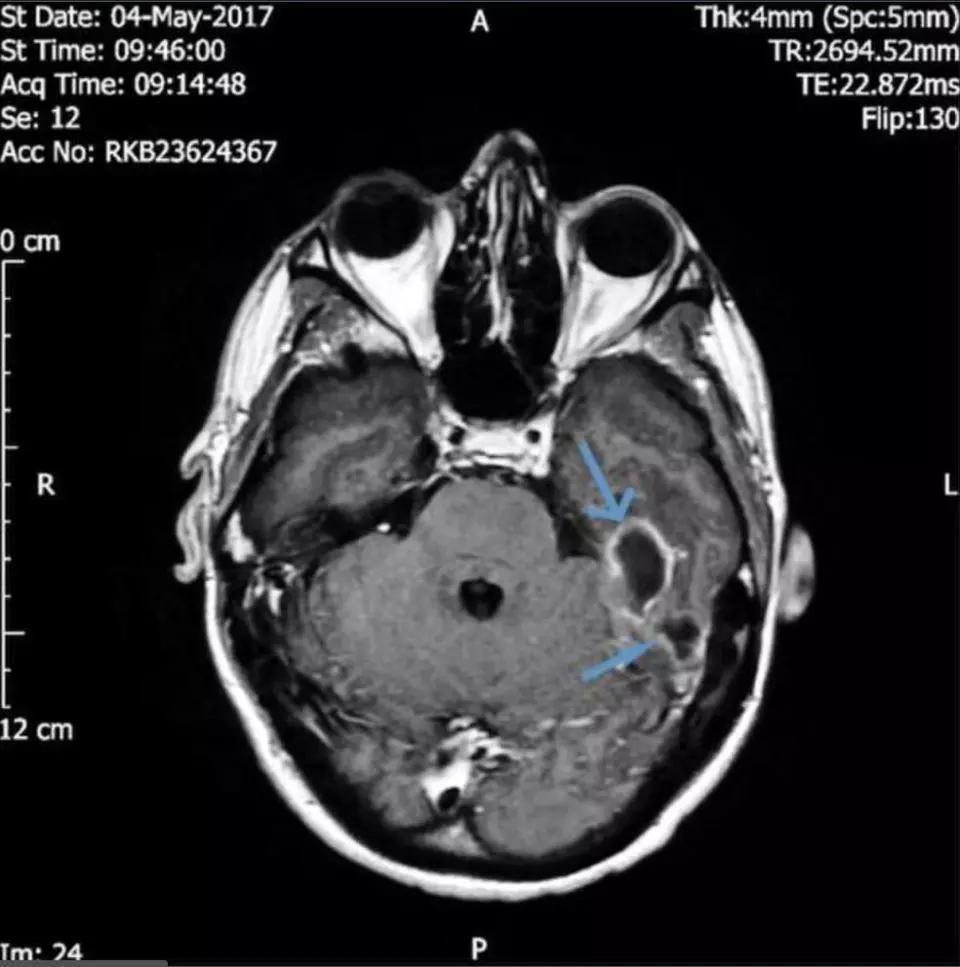

随着时间推移,感染已蔓延至大脑,从而引发了癫痫。

医学团队的CT扫描显示:他的头骨下靠近左耳道的位置有两块充满脓液的肿块,再晚治疗情况就危险了。

为有效消除感染,医生进一步寻找着致病的根源。

终于在脑成像的帮助下他们发现男子的耳道中有一个异物。经过鉴定,导致严重感染的东西是一小撮棉花。

原来,这位小伙洗完澡后,有用棉签清理耳道的习惯。但从没想过会造成这样的后果。

小伙的主治医生表示,癫痫发作可能由感染产生的毒性或者对大脑的压力引起。

幸亏救治及时,否则后果不堪设想!